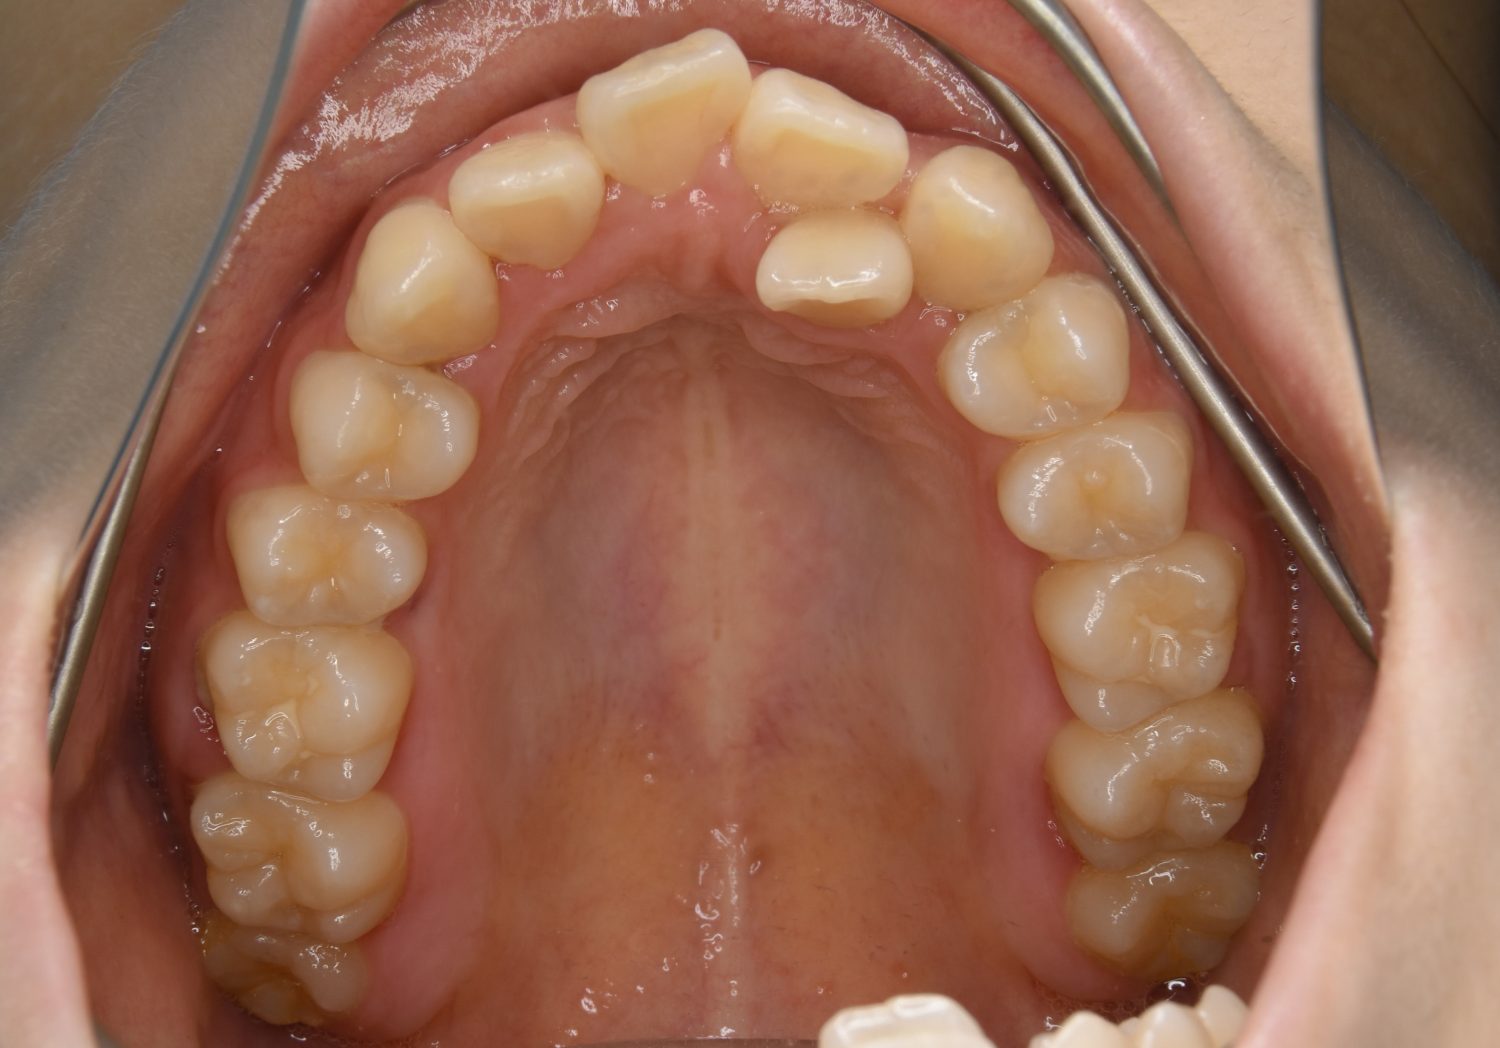

叢生の症例紹介②

Before

After

主訴

歯の凸凹を治したい。

治療内容

アライナー(インビザライン)にて非抜歯で治療を行いました。

上下前歯部に叢生(凸凹)が認められる状態でした。歯列の遠心移動を行うことで機能面および審美面が改善されました。